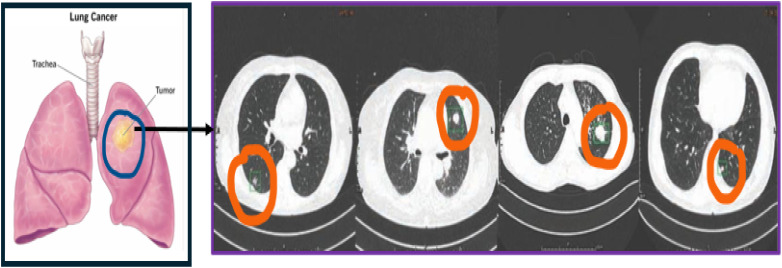

Lung cancer, the treacherous malignancy affecting the respiratory system of a human body, has a devastating impact on the health and well-being of an individual. Due to the lack of automated and noninvasive diagnostic tools, healthcare professionals look forward toward biopsy as a gold standard for diagnosis. However, biopsy could be traumatizing and expensive process. Additionally, the limited availability of dataset and inaccuracy in diagnosis is a major drawback experienced by researchers. The objective of the proposed research is to develop an automated diagnostic tool for screening of lung cancer using optimized hyperparameters such that convolutional neural network (CNN) model generalizes well for universally obtained computerized tomography (CT) slices of lung pathologies. The aforementioned objective is achieved in the following ways: (i) Initially, a preprocessing methodology specific to lung CT scans is formulated to avoid the loss of information due to random image smoothing, and (ii) a sine cosine algorithm optimization algorithm (SCA) is integrated in the CNN model, to optimally select the tuning parameters of CNN. The error rate is used as an objective function, and the SCA algorithm tries to minimize. The proposed method successfully achieved an average classification accuracy of 99% in classification of lung scans in normal, benign, and malignant classes. Further, the generalization ability of the proposed model is tested on unseen dataset, thereby achieving promising results. The quantitative results prove the efficacy of the system to be used by radiologists in a clinical scenario.